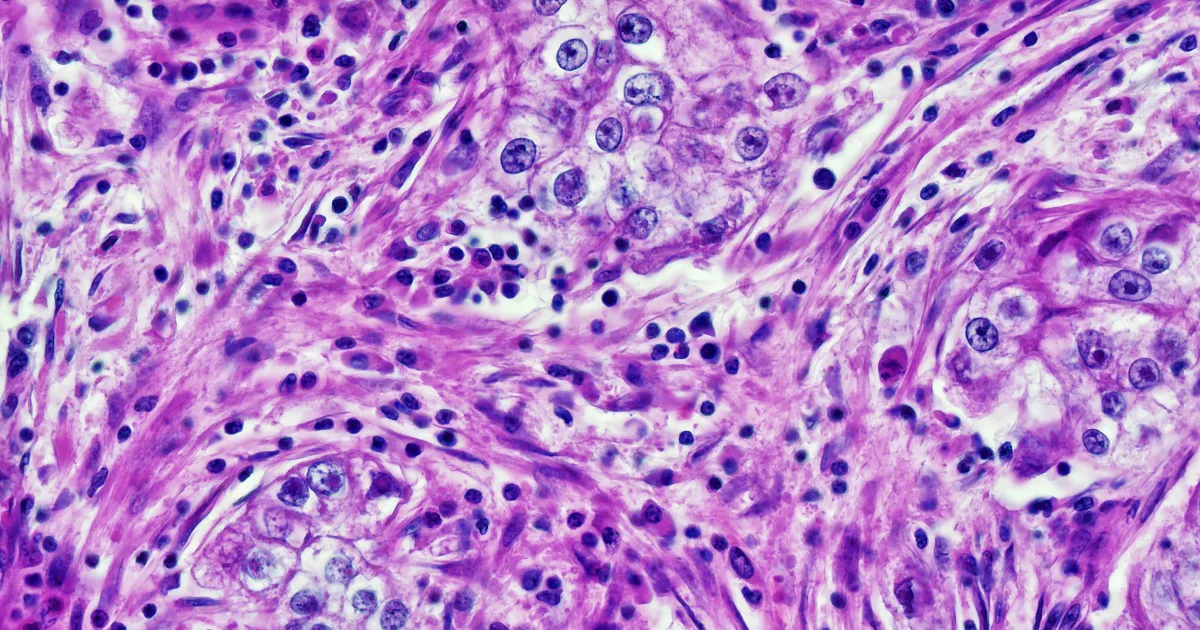

there were surprising findings published in the journal cell report medicineShows that four major AI-augmented pathology diagnostic systems vary in accuracy depending on patients, The disturbing thing is that AI is extracting demographic data – age, gender and race – directly from pathology slides, a feat that is impossible for human doctors.

To conduct the study, Harvard University researchers combed through nearly 29,000 cancer pathology images from approximately 14,400 cancer patients. Their analysis found that deep learning models displayed worrying biases 29.3 percent of the time — in other words, on about a third of all diagnostic tasks assigned to them.

To give a concrete example, AI tools were able to specifically identify samples taken from black people. The authors wrote that these cancer slides had higher numbers of atypical, neoplastic cells and fewer supporting elements than white patients, allowing the AI to eliminate them, even though the samples were anonymized.